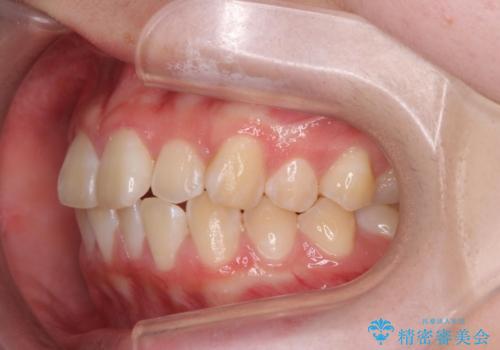

前歯のがたつき気になる。インビザラインモデレート

- 前歯のがたつきが気になるとの事で来院。

マウスピース矯正希望でしたのでインビザラインモデレートで治療を行いました。

がたつきが無くなり満足して頂けました。